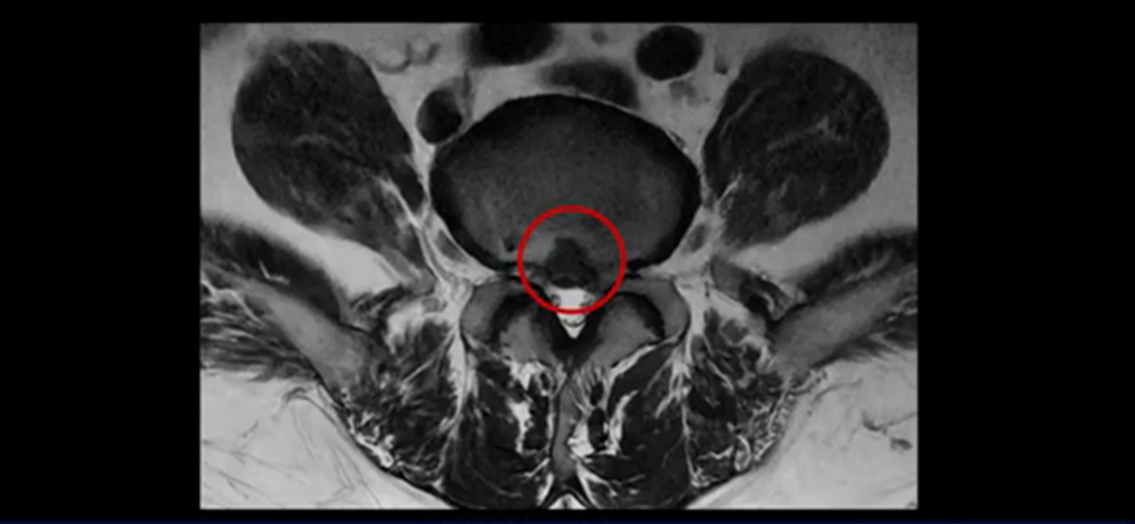

가운데로 심하게 밀려 나와 있는데요.

또 4번 5번에는 협착으로 척추관이 많이 좁아져 있습니다.

또 왼쪽 신경 가지들이 빠져 나가는 신경구멍들이 여러 마디가 좁아져 있습니다.

이런 이유들 때문에 왼쪽 엉덩이부터 종아리, 발가락까지 저리고 아픈 겁니다. 그래서 서둘러 병원에 가셨는데요. 그래서 서둘러 병원에 가셨는데요. 여러분이 꼭 아셔야 할 게 이렇게 다리가 심하게 저리고 아프면 X-ray만 찍을 게 아니고 MRI를 찍어 보시는 게 맞습니다. X-ray로는 디스크가 터졌는지 신경구멍이 좁아진 협착이 있는지를 정확히 할 수가 없습니다. 그래서 이분은 당장 아픈데 해결이 안 되니까 제주도에서 유명하다는 한의원으로 갔습니다.